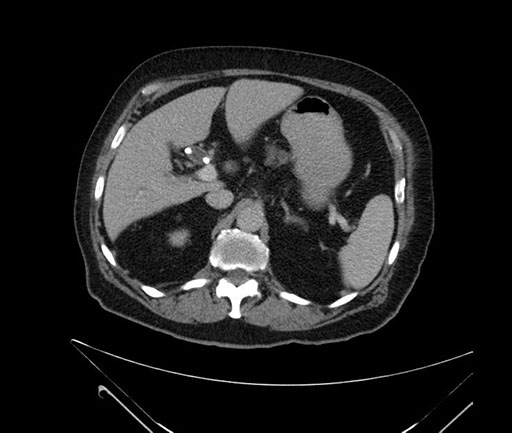

Whipple (pancreaticoduodenectomy) [case 7]

Axial - stented

Imaging analysis

Based on your CT findings, which issue(s) would give reason for "planned slowing down moment(s)" in this case?

Considering a standard Whipple procedure, what step(s) of the operation would you do differently in this case?